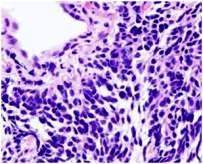

1. Mikrocelularni (sitnoćelijski, SCLC) karcinom

pluća se javlja u 20% slučajeva i ima tendeciju ranog širenja

putem krvi, najćešče u mozak, jetru, kosti, nadbubrežne žlezde, pušenje

je skoro uvek glavni faktor nastanka mikrocelularnog karcinoma.

2. Nemikrocelularni (nesitnoćelijski, NSCLC) karcinom

pluća je ćešća histološka forma i javlja se u 80% slučajeva

. Postoji više tipova nemikrocelularnog karcinoma: